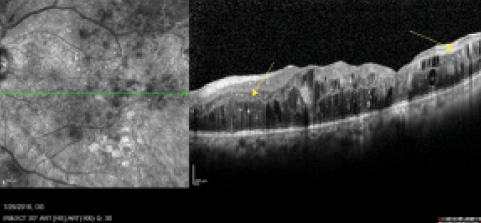

Figure 1. Scan length of raster (6 mm) allows only partial visualization of pathology.

Occasionally there is pathology that extends beyond the central macula (Figure 1). When the macular pathology runs off the screen, I have taught my technicians to change the width of the raster scan in real time to image the entire area (Figure 2). Lesions or pathology in the midperiphery, temporal macula, or nasal areas can also be imaged easily, thanks to longer-width raster scans, real-time fundus imaging, and optional fixation choices.